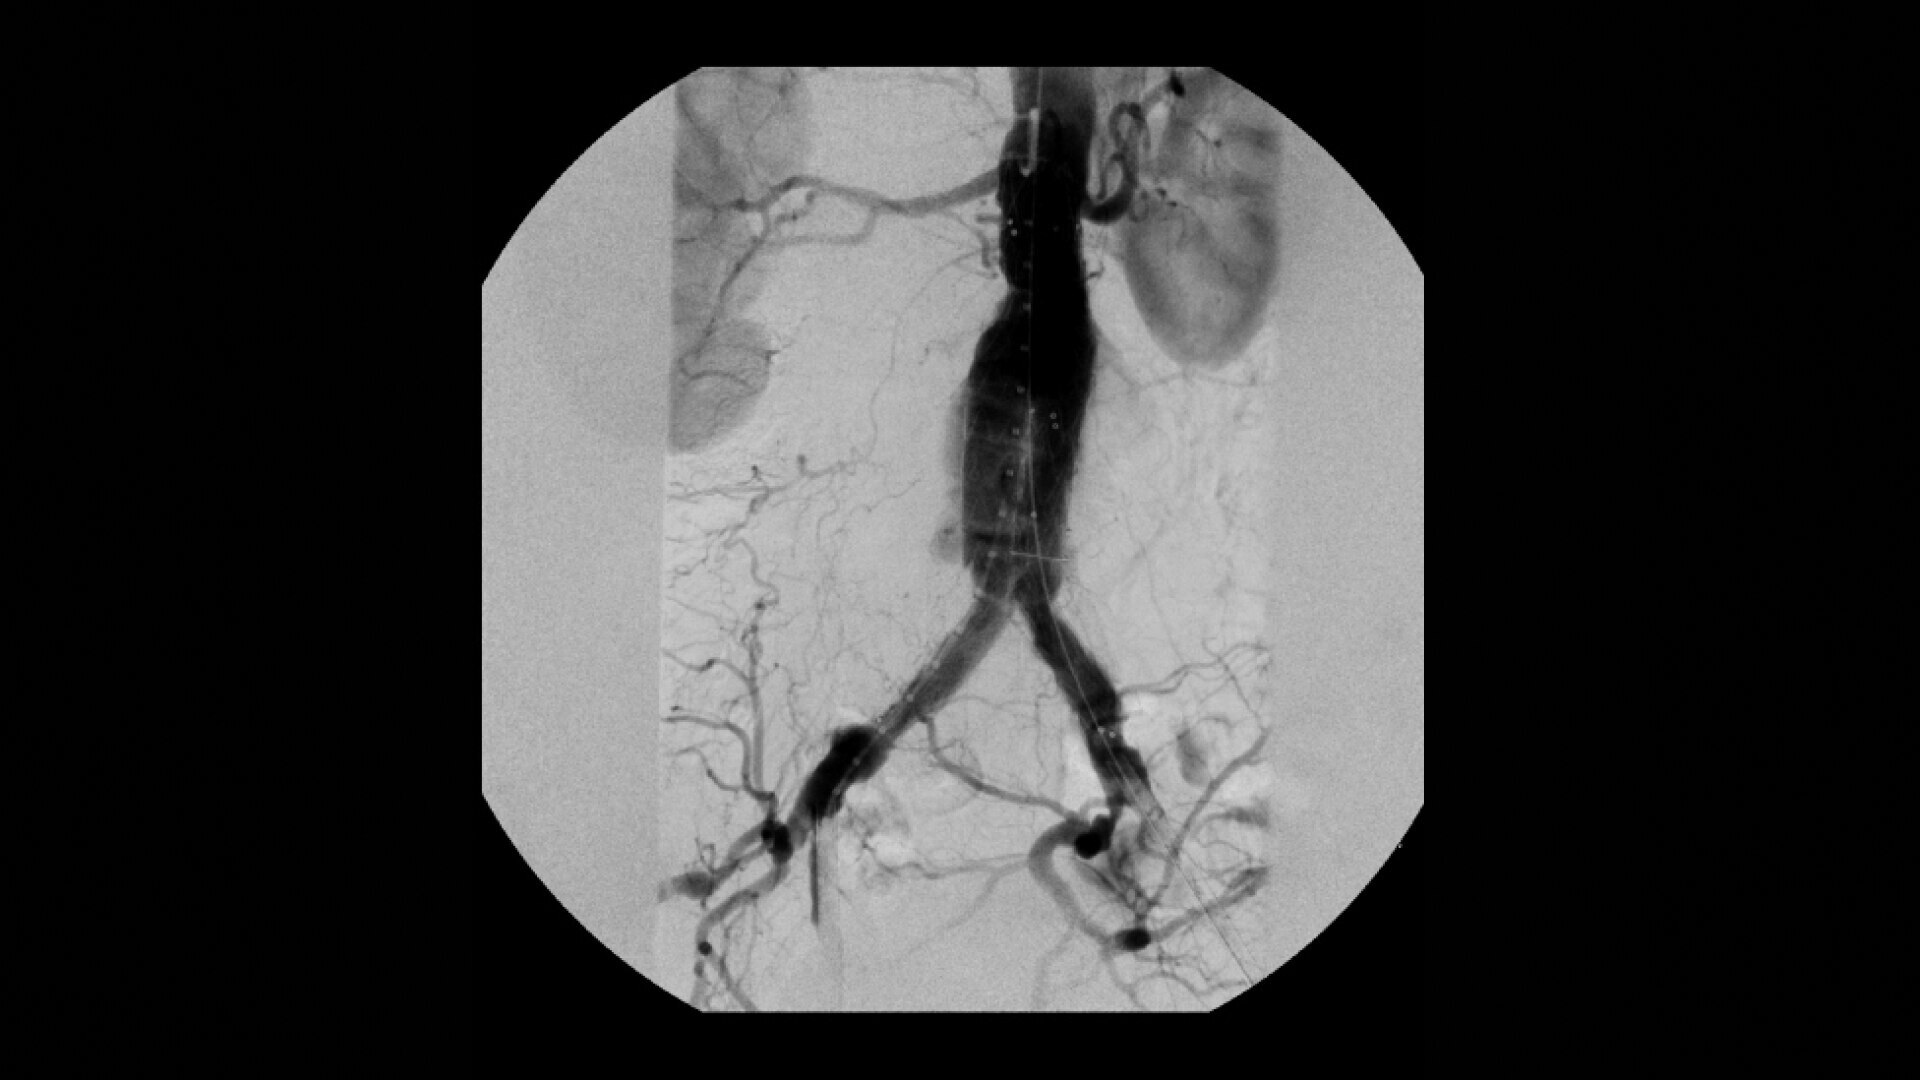

OEC C-arms are used by interventionalists and surgeons to obtain vascular imaging during peripheral to contrast run-off procedures. Superb resolution, even in the presence of motion, enables easy identification of anatomical landmarks and the extremity of the catheter, even as catheter tip moves.

Perform a full leg Bolus Chase in one contrast run with a Preset Profile that includes Motion Tolerant Subtraction, that dynamically adjusts image quality based on presence of motion.

During contrast run-off procedures, easily select contrast type with positive (e.g. Iodine) or negative (e.g. Carbon Dioxide) during subtraction. The OEC Elite CFD cardiovascular package also includes Roadmapping.

•Abdominal aortic aneurysm (AAA) stent and balloon deployment

• Infrarenal aortic aneurysm repair

• Recanalization and stent placement in iliac arteries

• Recanalization of the superior mesenteric artery

• Stent implant in peripheral artery

• Vascular long lesion treatment